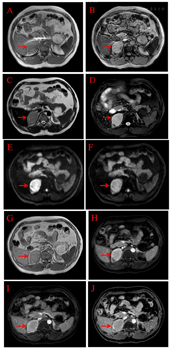

注:2012年4月20日肾上腺增强CT:动脉期(图A),门脉期(图B),平衡期(图C),平扫(图D);2012年12月26日肾上腺增强CT动脉期(图E),平扫期(图F);2015年8月19日肾上腺CT平扫(图G);2018年4月24日肾上腺CT平扫(图H)。右侧肾上腺占位(如箭头所示)

醋酸氢化可的松起始剂量60 mg/d,根据病情调整剂量。2012年12月26日复查肾上腺CT平扫+增强(图2 E-F)示右侧肾上腺占位性变(5.6 cm×4.0 cm×4.1 cm)体积较未治疗前缩小约33%。2012年12月26日盆腔CT示:盆腔内可见子宫及附件结构,子宫大小、形态及密度未见异常。左侧附件见一大小约1.8 cm×1.4 cm囊性肿块,增强时囊壁强化。2013年5月份自觉双侧乳房增大、胀痛,自行将醋酸氢化可的松减量至40 mg/d后自觉乳房无继续增大,且胀痛减轻。根据患者治疗后复查的结果表明该患者原右侧肾上腺占位可能为皮质过度增生的结果,且患者强烈要求保留其男性社会性别,遵从患者意愿,醋酸氢化可的松减量为40 mg/d。2015年1月患者自行将醋酸氢化可的松减量至20 mg/d,2015年8月19日复查肾上腺CT示右侧肾上腺占位性病变与前比较未见明显变化(图2 G),建议予醋酸氢化可的松15 mg/d,但其自行减量至10 mg/d。2018年4月20日复查肾上腺CT示:右侧肾上腺占位性病变与前比较仍无明显变化(图2 H)。2021年4月1日双侧肾上腺MRI平扫+增强示:右侧肾上腺去见一稍短T1长T2信号灶,信号欠均匀,DWI呈高信号,其内见斑片状短T1长T2脂肪信号灶,压脂序列呈低信号,增强扫描明显不均匀强化区,其内脂肪成分未见强化,周围见斑片状延迟强化区,大小约5.0 cm×3.9 cm×4.9 cm;左侧肾上腺较同侧膈肌厚,最厚处约0.9 cm。双侧肾上腺与周围结构分界清楚。双侧肾上腺水平腹膜后淋巴结未见重度。提示右侧肾上腺占位较2018年4月缩小约4%,较未治疗前缩小约30%(图3)。阴囊、睾丸、阴阜超声提示:会阴部探及可显示腹腔内未见正常睾丸及附睾组织回声。治疗前后各项指标变化(图1)。